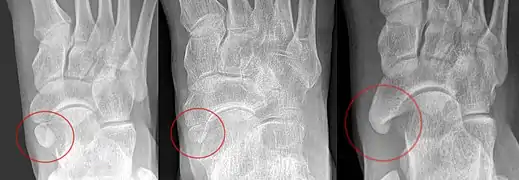

Cheville

Les os accessoires de la cheville comprennent principalement :

- L'os subtibiale qui a une prévalence d'environ 1 % et est issu d'un centre d'ossification secondaire du tibia distal qui apparaît au cours de la première année de vie et qui, chez la plupart des gens, fusionne avec la diaphyse vers 15 ans chez la femme et vers 17 ans chez l'homme.

- L'os subfibulare, avec une prévalence d'environ 0,2%.

Os naviculaire accessoire

Un os naviculaire accessoire se développe parfois devant la cheville vers l'intérieur du pied. Cet os peut être présent chez environ 2 à 21 % de la population générale et est généralement asymptomatique[10],[11],[12]. Lorsqu’il est symptomatique, une intervention chirurgicale peut être nécessaire.

La classification Geist divise les os naviculaires accessoires en trois types[12] :

- Type 1 : os sésamoïde de 2 à 3 mmm dans le tendon distal du muscle tibial postérieur, généralement asymptomatique,

- Type 2 : osselet triangulaire ou en forme de cœur mesurant jusqu'à 12 mm, qui représente un centre d'ossification secondaire relié à la tubérosité naviculaire par un connecteur 1–2 mm de fibrocartilage ou de cartilage hyalin, des parties du tendon du muscle tibial postérieur s'insèrent parfois sur l'osselet accessoire, ce qui peut provoquer un dysfonctionnement et donc des symptômes,

- Type 3 : Un os corné présentant une tubérosité naviculaire médiale élargie, parfois symptomatique en raison de la formation d’oignons.

Os trigone

L'os trigone (ou astragale surnuméraire ou astragale accessoire) provient de l'échec de la fusion du tubercule latéral du processus postérieur du talus . On estime qu'il est présent chez 7 à 25 % des adultes[9].

Il peut être confondu avec une fracture par avulsion des tubercules latéral ou médial du processus postérieur du talus.

Dans la plupart des cas, l'os trigone passe inaperçu, mais dans certaines blessures à la cheville, il peut rester coincé entre le talon et les os de la cheville provocant une inflammation des structures environnantes[13].